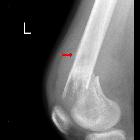

Teenager who

after bumping their leg 1 year ago has had a painful lump in the shin. AP radiograph of the tibia and fibula (left) with a magnified view (right) shows a lesion in the diaphysis of the tibia with permeative cortical destruction and associated periosteal reaction and a Codman’s triangle.The diagnosis was osteosarcoma of the tibia.

nicht verwechseln mit: Codman-TumorA Codman triangle is a type of periosteal reaction seen with aggressive bone lesions. The periosteum does not have time to ossify with shells of new bone (e.g. as seen in a single layer and multilayered periosteal reaction) in aggressive lesions, so only the edge of the raised periosteum will ossify.